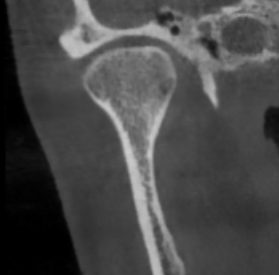

Перед началом лечения я провожу часовую первичную консультацию. Для этой встречи вам необходимо сделать «МРТ ВНЧС» и «КЛКТ двух челюстей с захватом ВНЧС в привычном прикусе».

Во время консультации мы смотрим и анализируем ваши исследования. Я подробно объясняю строение ВНЧС, показываю все причинные факторы вашей проблемы, отвечаю на все вопросы «Почему?»